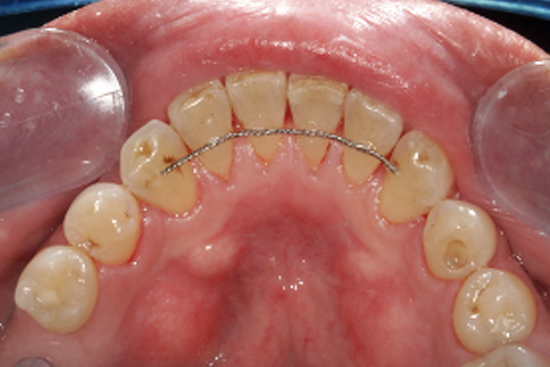

部分矯正の症例

治療前

治療後

| 主訴 | 歯並びが気になる |

|---|---|

| 治療期間 | 7ヶ月 |

| 治療費 | 50万(税抜) |

| 治療内容 | 部分矯正 |

| 治療の リスク |

治療中は清掃しにくいため 虫歯になりやすい |